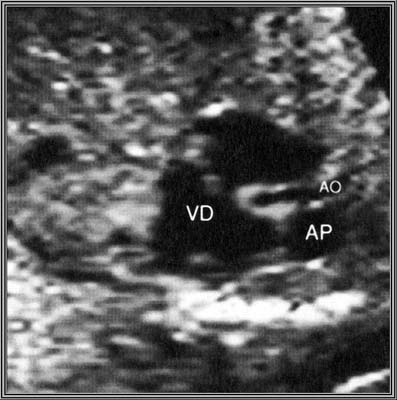

Atrésie Ao